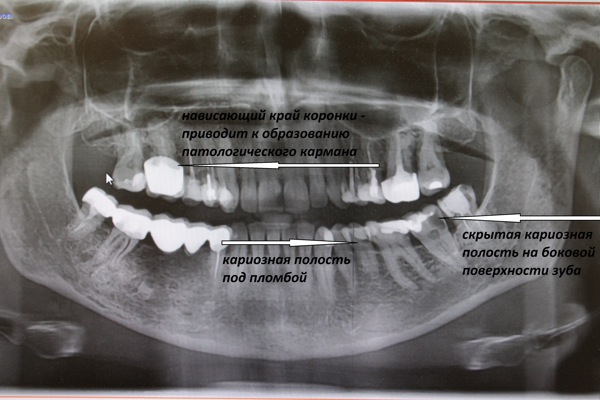

Дентальные снимки и диагностика кариеса